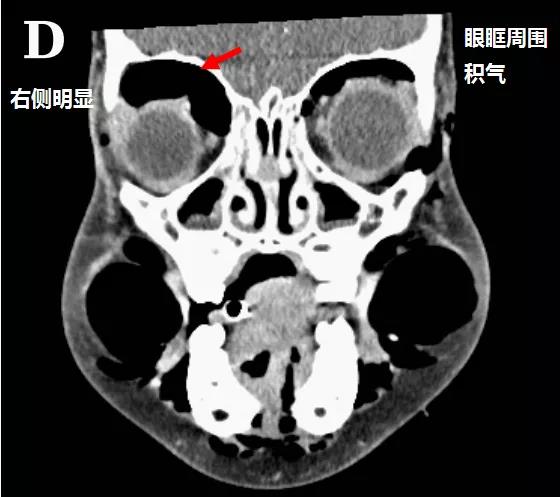

頭顱、胸部CT提示廣泛皮下氣腫、縱隔氣腫、心包積氣、甚至眼眶周圍都積氣,眼球突出!頸部無感染征象,腸管無破裂征象,看來氣體還是來自肺部。但是,肺部無感染、無肺大泡、無劇烈咳嗽,只有間質性肺氣腫。縱隔氣腫、皮下氣腫的治療,核心是根除病因,切開引流效果不像氣胸那么理想,而且縱隔切開引流還存在手術風險。找不到病因,如何是好?考慮患者是過敏體質,有皮疹,繼續(xù)呼吸機輔助呼吸,先治療過敏,肌肉注射腎上腺素、靜脈注射類固醇激素和抗組胺藥、吸入支氣管擴張劑等。經上述治療,臨床表現(xiàn)和影像學方面都有迅速的改善。隨后拔出氣管導管,口服類固醇激素出院,門診隨訪。